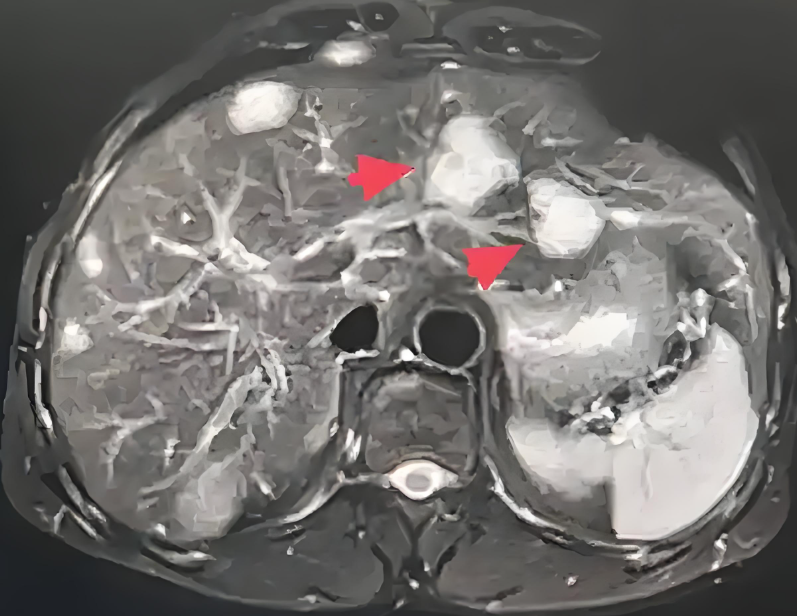

肝血管瘤是一种常见的肝脏良性肿瘤,多为海绵状血管瘤,由扩张的血窦和纤维间质组成,发病机制可能与先天性血管发育异常激素水平等因素有关,通常无明显症状,多在体检或影像学检查时发现肝血管瘤的危险性需分情况讨论一般情况多数情况下,肝血管瘤危险程度较低瘤体较小时直径通常小于5厘米。

肝内血管瘤是指肝脏内出现的血管瘤样病变,属于常见的肝脏良性肿瘤其本质是肝脏内血管的异常增生形成的肿瘤样结构,通常由扩张的血管腔和纤维结缔组织构成,并非真正意义上的恶性肿瘤根据病变特征,肝内血管瘤可分为以下类型单个血管瘤肝脏内孤立存在的血管瘤,占多数病例多发血管瘤同时存在多个。